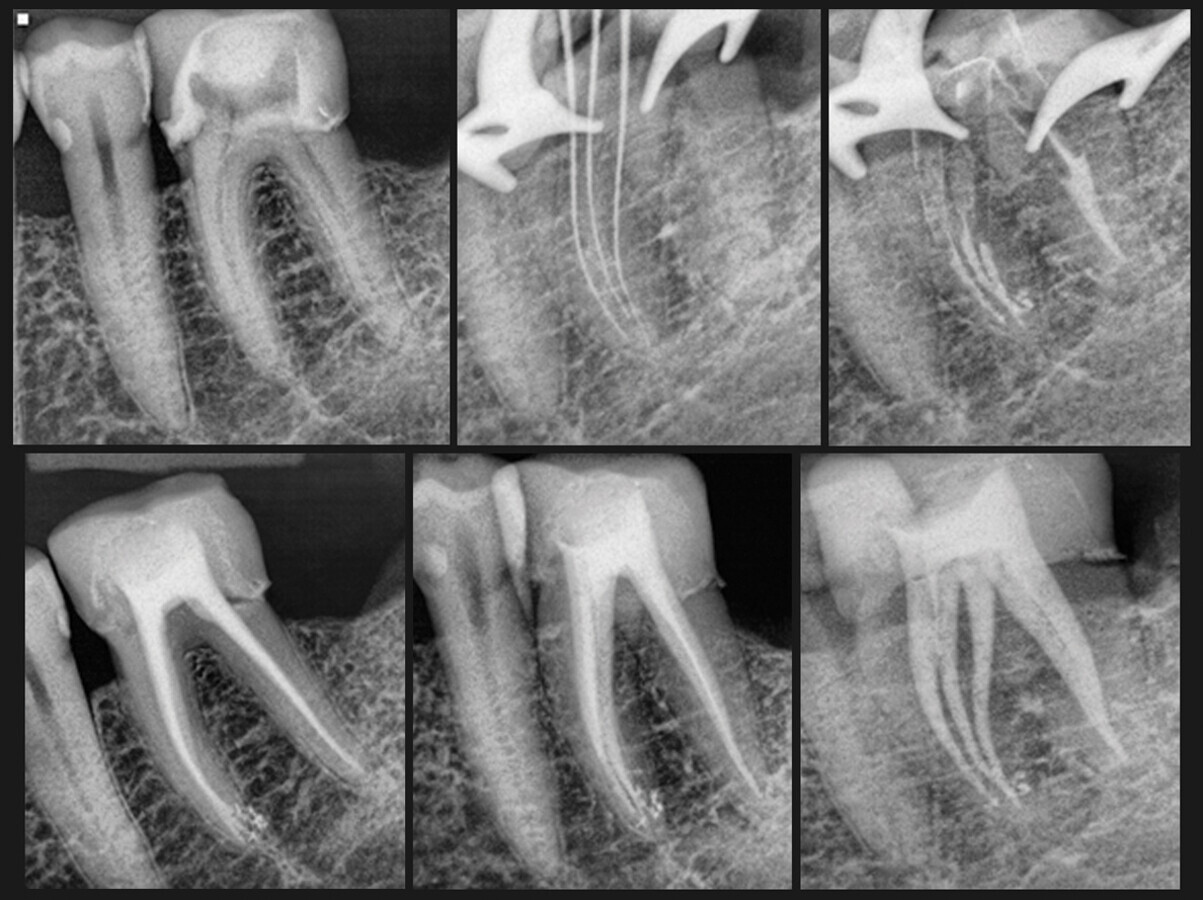

Designed by an endodontist for endodontists and endo-savvy dentists, this unique 30 mm-long bur has a narrow shaft with geometric features that maintain the view corridor to the target area and reduce shaft impingement while providing the stiffness required for troughing-type procedures.

The perfect companion to the fluted carbide Munce Discovery Burs, the 4 mm-long diamond portion that tapers down to 0.4 mm at the very tip refines the trough already discovered and explored without creating heat or the pesky dust of ultrasonic tips — and relative to ultrasonic tips, these burs are cost-effective, especially considering they don’t break.

With its slow rotation, the TruGrit Trough Refiner offers increased operational control for refining the isthmus between the canals of molars, the complex isthmus systems of bicuspids and for dissecting the cement-line around posts.